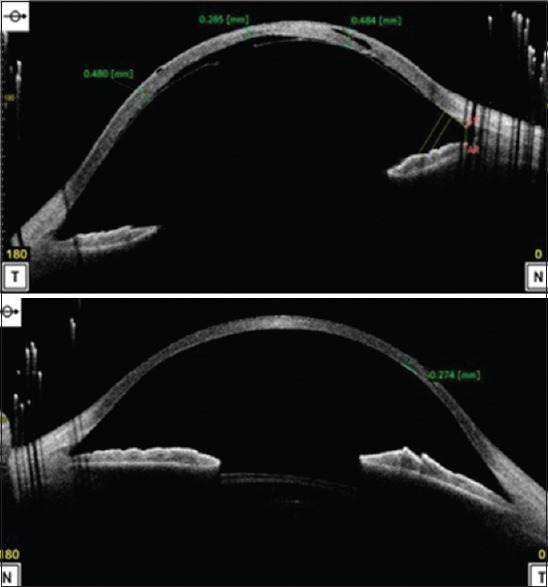

To describe the management of post-traumatic Descemet's membrane detachment and intraoperative corneal rupture in a known case of Ehlers-Danlos Syndrome (EDS). A 7-year-old child, a known case of EDS, presented with Descemet's membrane tear in the right eye for which intracameral sulfur hexafluoride (SF6) and descemetopexy were done. Intraoperative spontaneous rupture of the cornea was noted during descemetopexy which was managed using cyanoacrylate glue and bandage contact lens. We successfully used cyanoacrylate tissue adhesive glue for sealing of corneal rupture suggesting that it can be considered a treatment option for such cases where there is a lack of tissue strength for suturing.